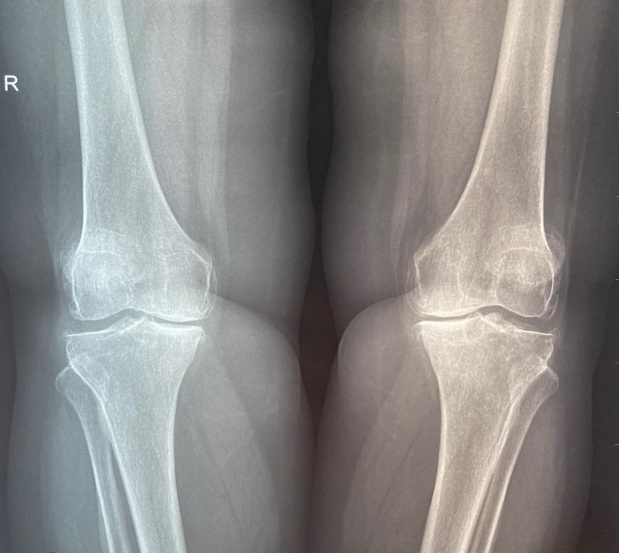

膝关节骨关节炎(KOA)是一种渐进性疼痛疾病,久而久之会导致功能丧失和残疾。早期诊断和正确治疗对于防止病情发展到影响生活质量的阶段至关重要。新的成像方法和设备的开发有助于在症状出现之前检测出关节结构的变化。目前还没有获批的改变疾病的药物,因此目前的治疗方法是对症治疗,重点是减轻疼痛、改善功能并努力防止病情恶化导致残疾。

Knee osteoarthritis (KOA) represents a progressive and painful disease that in time can lead to loss of function and disability. Early diagnosis and correct treatment are essential in preventing the advancement of the condition to a stage where it can affect the quality of life. The development of new imagistic methods and devices can help detect changes in the structure of the join before the onset of symptoms. At the moment there are no disease- modifying drugs approved, so the current treatment is symptomatic, focusing on pain reduction, improving function and trying to prevent progression towards disability.